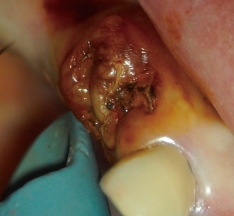

歯髄の焼灼、根管内外の感染組織や汚染物質の焼灼が行え、歯肉切除用のモードを選択することで、電気メスとしても使用可能です。

高周波通電により、チップ電極の先端部と接触した部位を発熱させることで、組織の焼灼・凝固・切開を行うことができます。

マイクロスコープ利用時の術野確保に有効です。